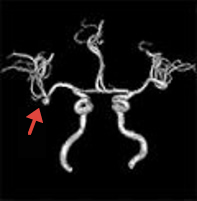

くも膜下出血の原因となる脳動脈瘤は、破裂前に発見することが可能です。小さな無症候性脳梗塞(いわゆる隠れ脳梗塞)や微小な脳内出血の痕跡も早期に発見することが可能ですので、今後の脳卒中予防の対策をとることが可能となります。

未破裂脳動脈瘤

(矢印)